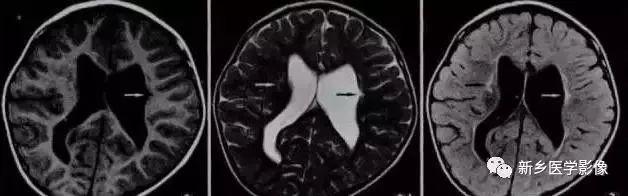

7.视-隔发育不良

是一种少见的先天发育畸形,主要包括:1.透明中隔缺如或发育不全,2.视神经、视交叉及漏斗部发育不良3.不同程度的下丘脑-垂体功能障碍。影像学表现可能很轻微,包括透明中隔缺如,视神经及视交叉变细,视神经管小,三脑室视隐窝扩大,双侧侧脑室扩大,侧脑室前角呈方形。多见于女性,可表现有尿崩症,视力障碍及丘脑下功能障碍。